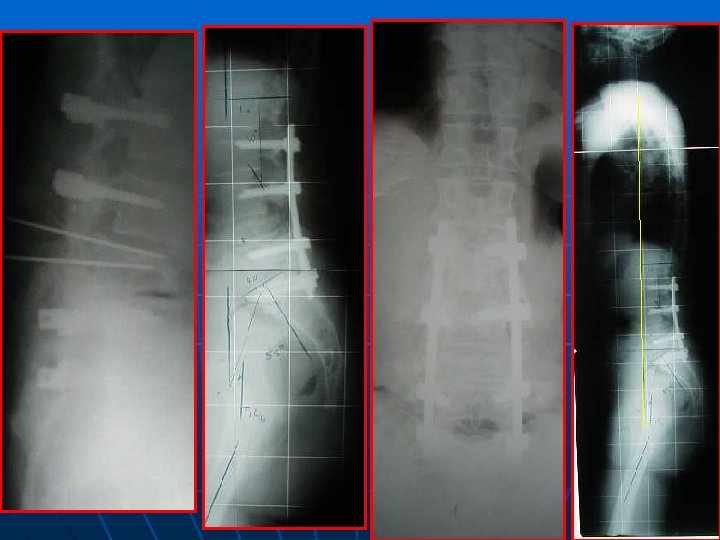

CLICHES GRAND FORMAT n INDICATIONS : * déséquilibre clinique frontal ou sagittal * scoliose et/ou modification de la courbure lombaire sur le profil ( LL, cyphose) * pas de corrélation entre l’IP et les autres paramètres pelviens * technique : debout, bras en légère antépulsion, base de crâne tête fémorale.

INCLURE OBLIGATOIREMENT LES TETES FEMORALES 0 SUR LES 2 INCIDENCES +++

CLICHES GRAND FORMAT n RESULTATS – PARAMETRES : * Face : C 7 ou T 1 ½ sacrum déséquilibre D ou G * Profil : ° équilibre si C 7 derrière disque L 5 -S 1 derrière têtes fémorales+++ ° déséquilibre positif ou négatif ° IP, PS, VP, LL, CT

52 ans, spondylo L 5 -S 1 grade I, Beaujon 10

+18 mois, Beaujon 80%